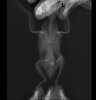

Попугай хохлится, припухлость на шее

Тема в разделе "ДРУГИЕ ЗАБОЛЕВАНИЯ. Плохой помет, рвота и др.", создана пользователем Millenium, 7 ноя 2020.